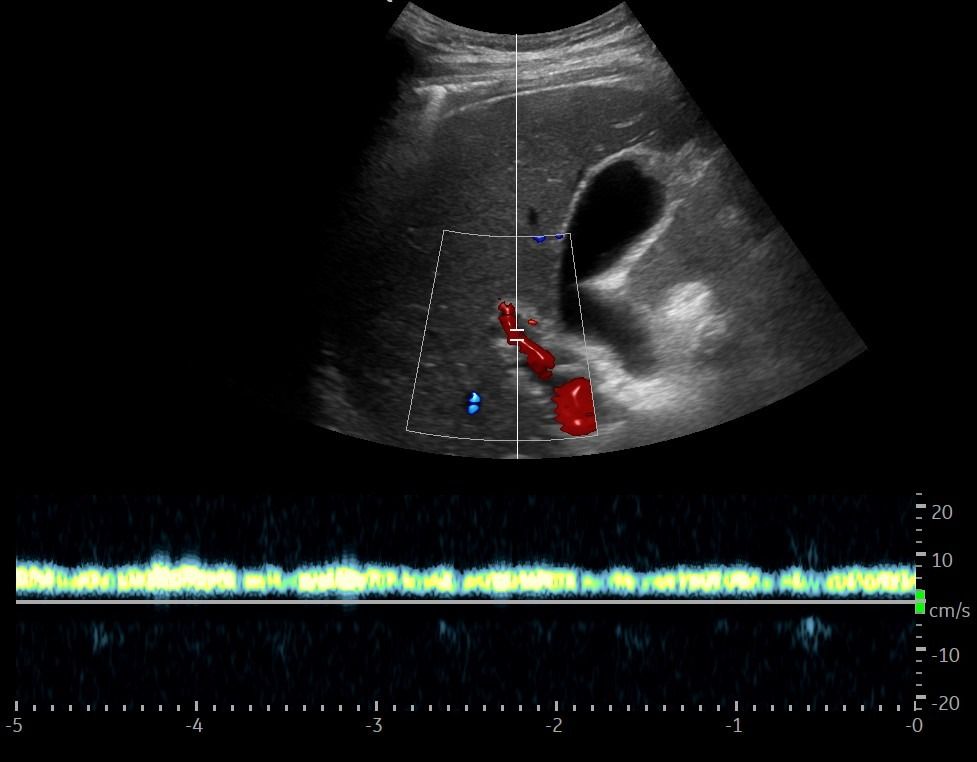

Με το Τriplex Σπληνοπυλαίου Άξονα αξιολογείται η πυλαία υπέρταση, συνήθως σε έδαφος χρόνιας ηπατοπάθειας και η βατότητα ή θρόμβωση της πυλαίας φλέβας και των ηπατικών φλεβών.